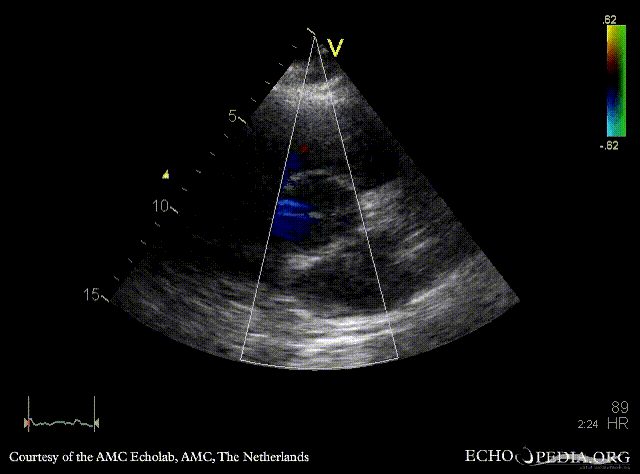

PSAX with Color Doppler: mild aortic regurgitation